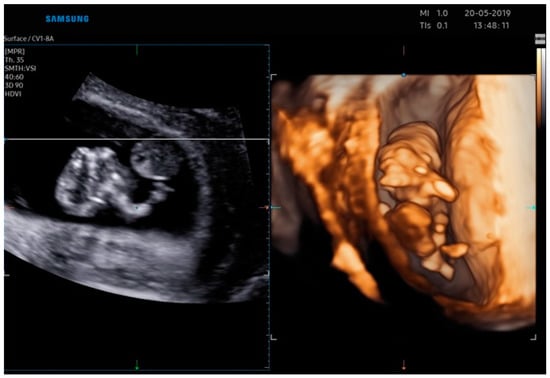

2.2. Case Report 2